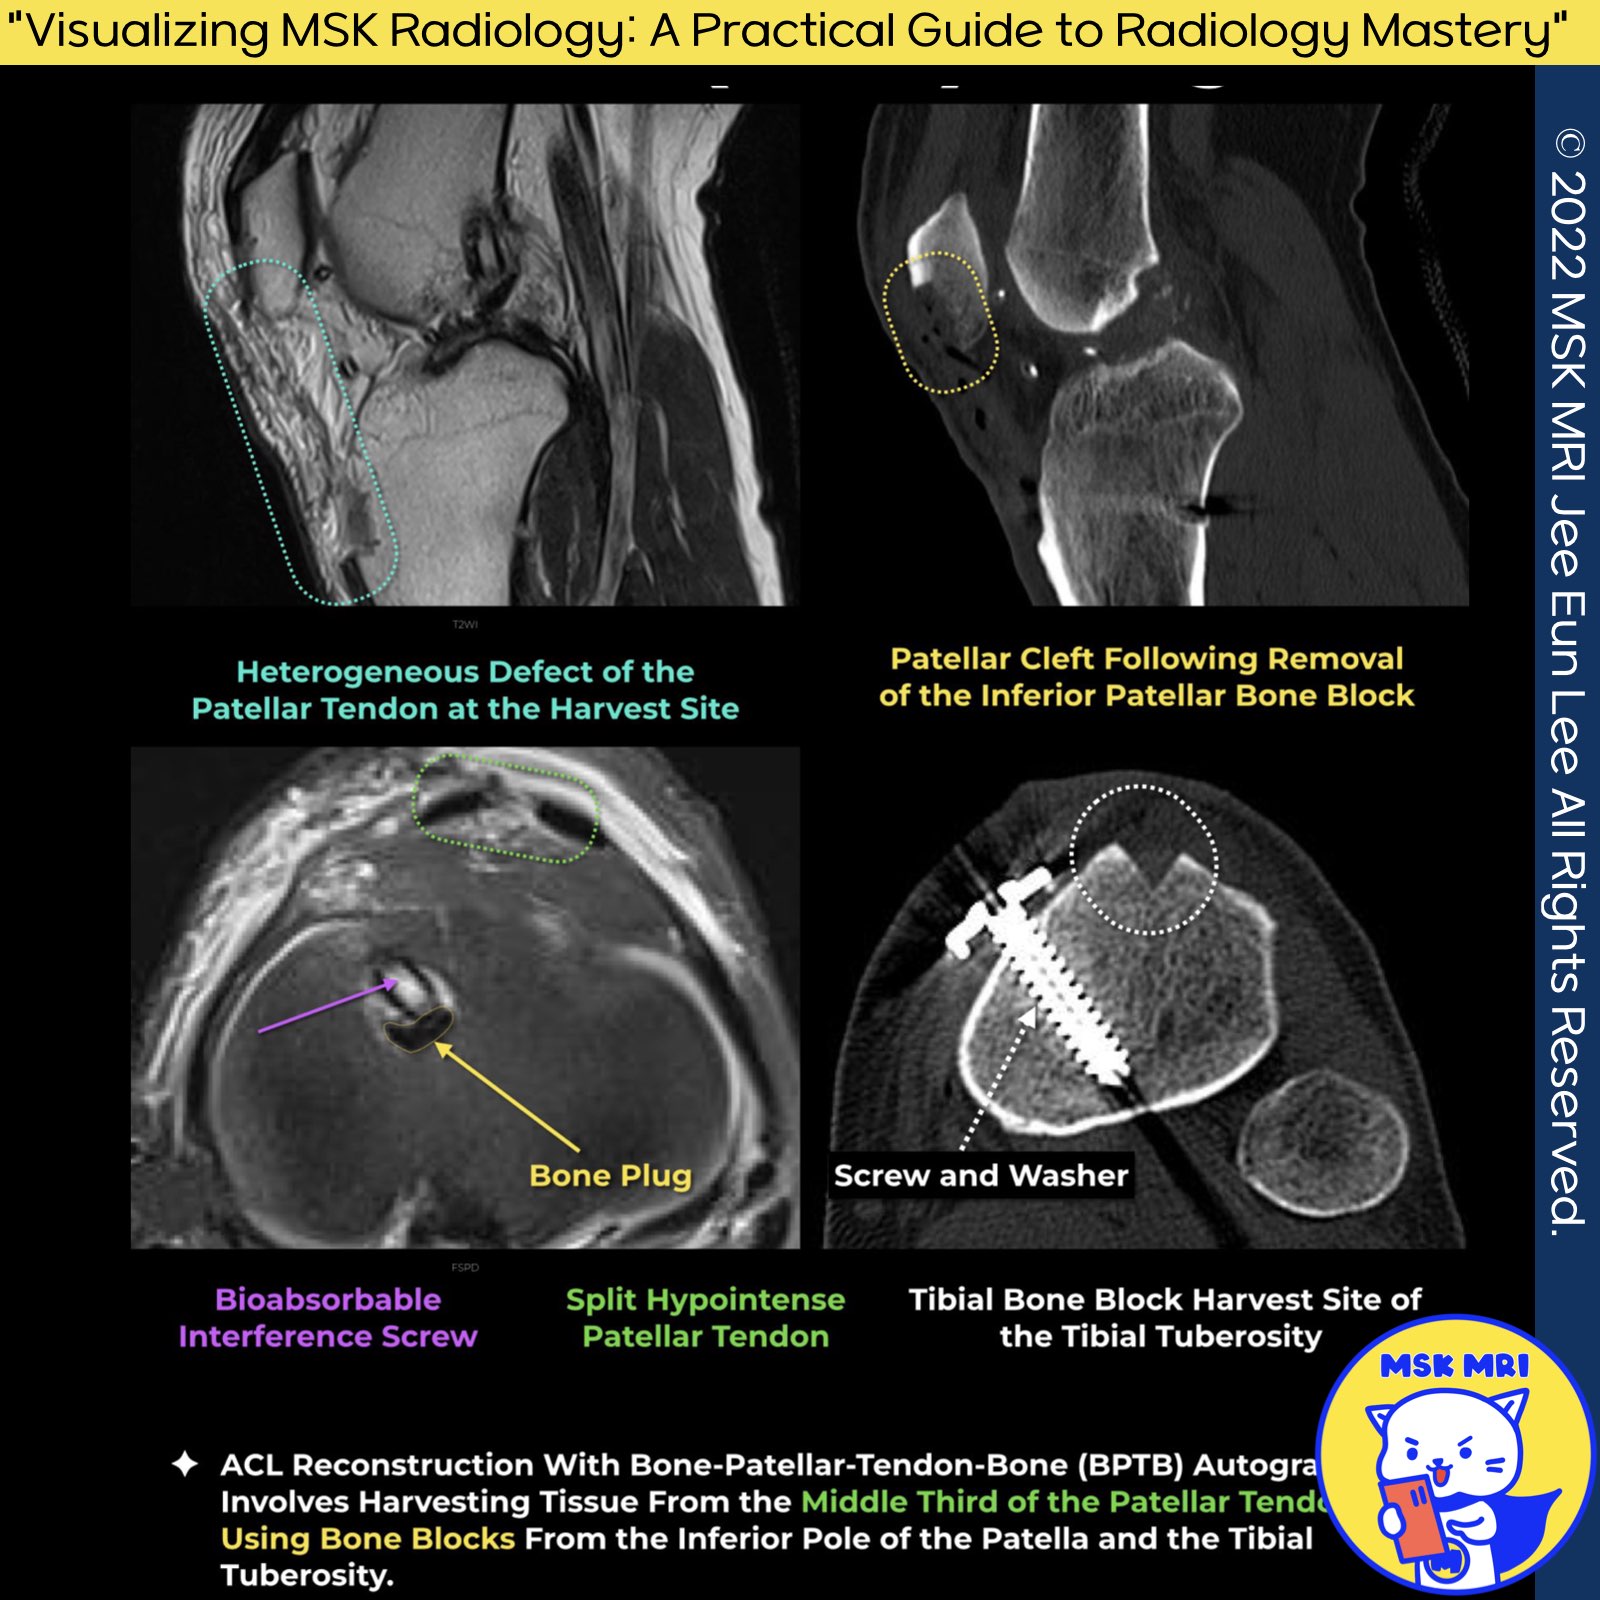

- Harvested from the central third of the patellar tendon with bone grafts from the inferior pole of the patella and tibial tuberosity

- Bone grafts initially anchored within the tunnels using interference screws

- Achieves deeper fixation through bone-to-bone healing, known to occur as early as 16 weeks following surgery